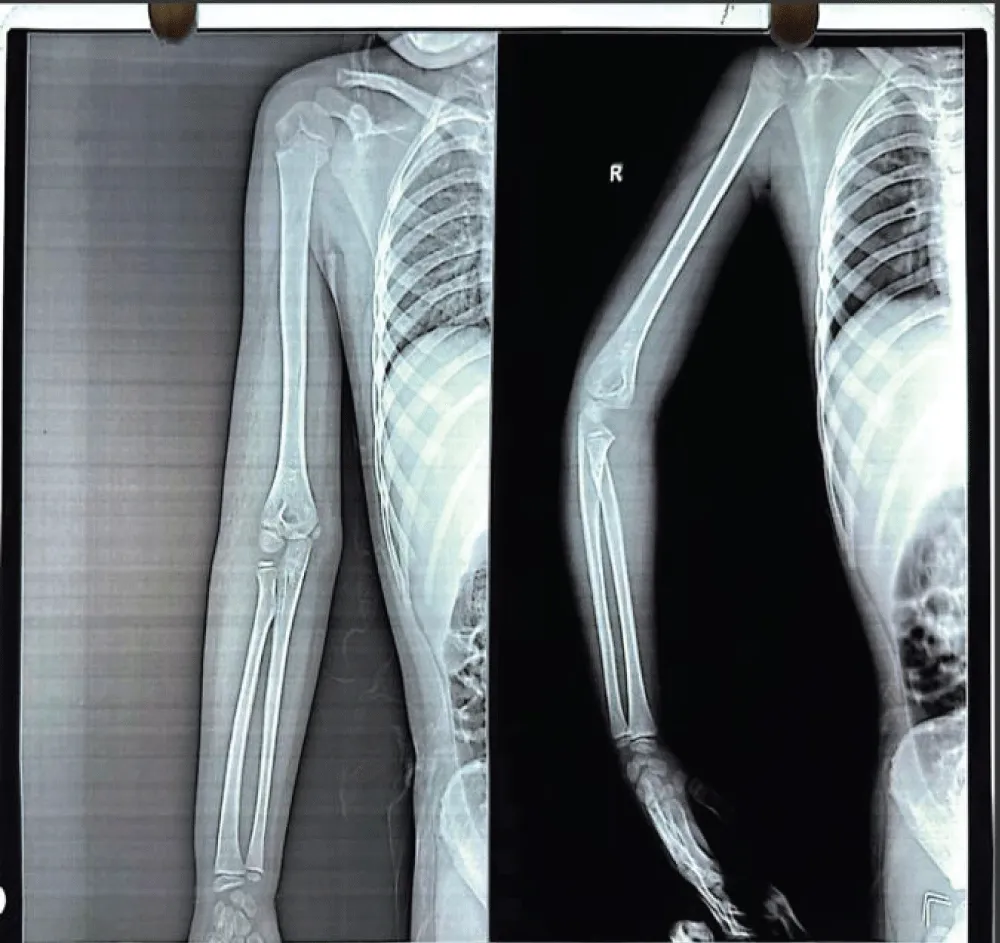

A mother with 6 year old female child presented to our Orthopedic Out Patient Department. She had not been able to move her right elbow in full range with restricted active and passive movements and appeared distressed. According to the informant (mother), she had been apparently well 2 months back when she was hit by rear wheels of a tractor while playing on the roadside. She developed pain and swelling in the elbow and was immediately rushed to the nearby hospital. Routine investigations, CT scan of abdomen and pelvis and X-ray of right elbow and hand were done. (Figures 1-3). All reports were normal except X-ray arm diagnosing undisplaced low lying supracondylar fracture of the right humerus (Figure 3). The child was admitted to the hospital and right upper limb was immobilized in an above-elbow plaster slab, with the elbow in 90o flexion (Figure 4). She was discharged after 4 days with reportedly normal radiographic findings.

Radiological imaging showed residual heterotopic ossification along the humerus, indicating incomplete resolution. Multiple radiographs of the right upper limb-including the arm, forearm, and elbow joint were taken during outpatient visits at the patient’s convenience and were compared over time to monitor progress (figure 7,8). A well-visualized radiograph obtained 10 months after the initial injury showed near-complete resolution of the heterotopic ossification (Figure 9).